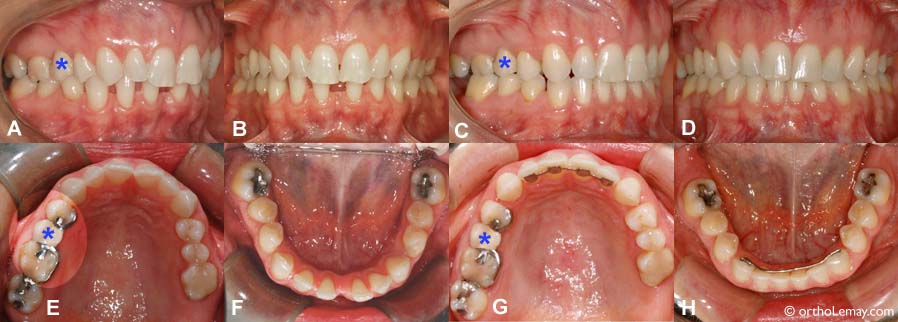

(A, B, F) Espaces interdentaires importants entre les dents antérieures inférieures.

(C, D, H) Après l’orthodontie, les espaces sont fermés et les dents rapprochées. Un fil de rétention est essentiel pour prévenir une ré-ouverture des espaces. À noter qu’il reste de légers espaces à droite (visibles en C et G). Cette patiente de 46 ans avait un pont papillon (indiqué par un astérisque *) qui empêchait tout mouvement des dents postérieures droit et a empêché la fermeture de ces légers espaces pour prévenir que le pont doive être refait si on désirait bouger ces dents.